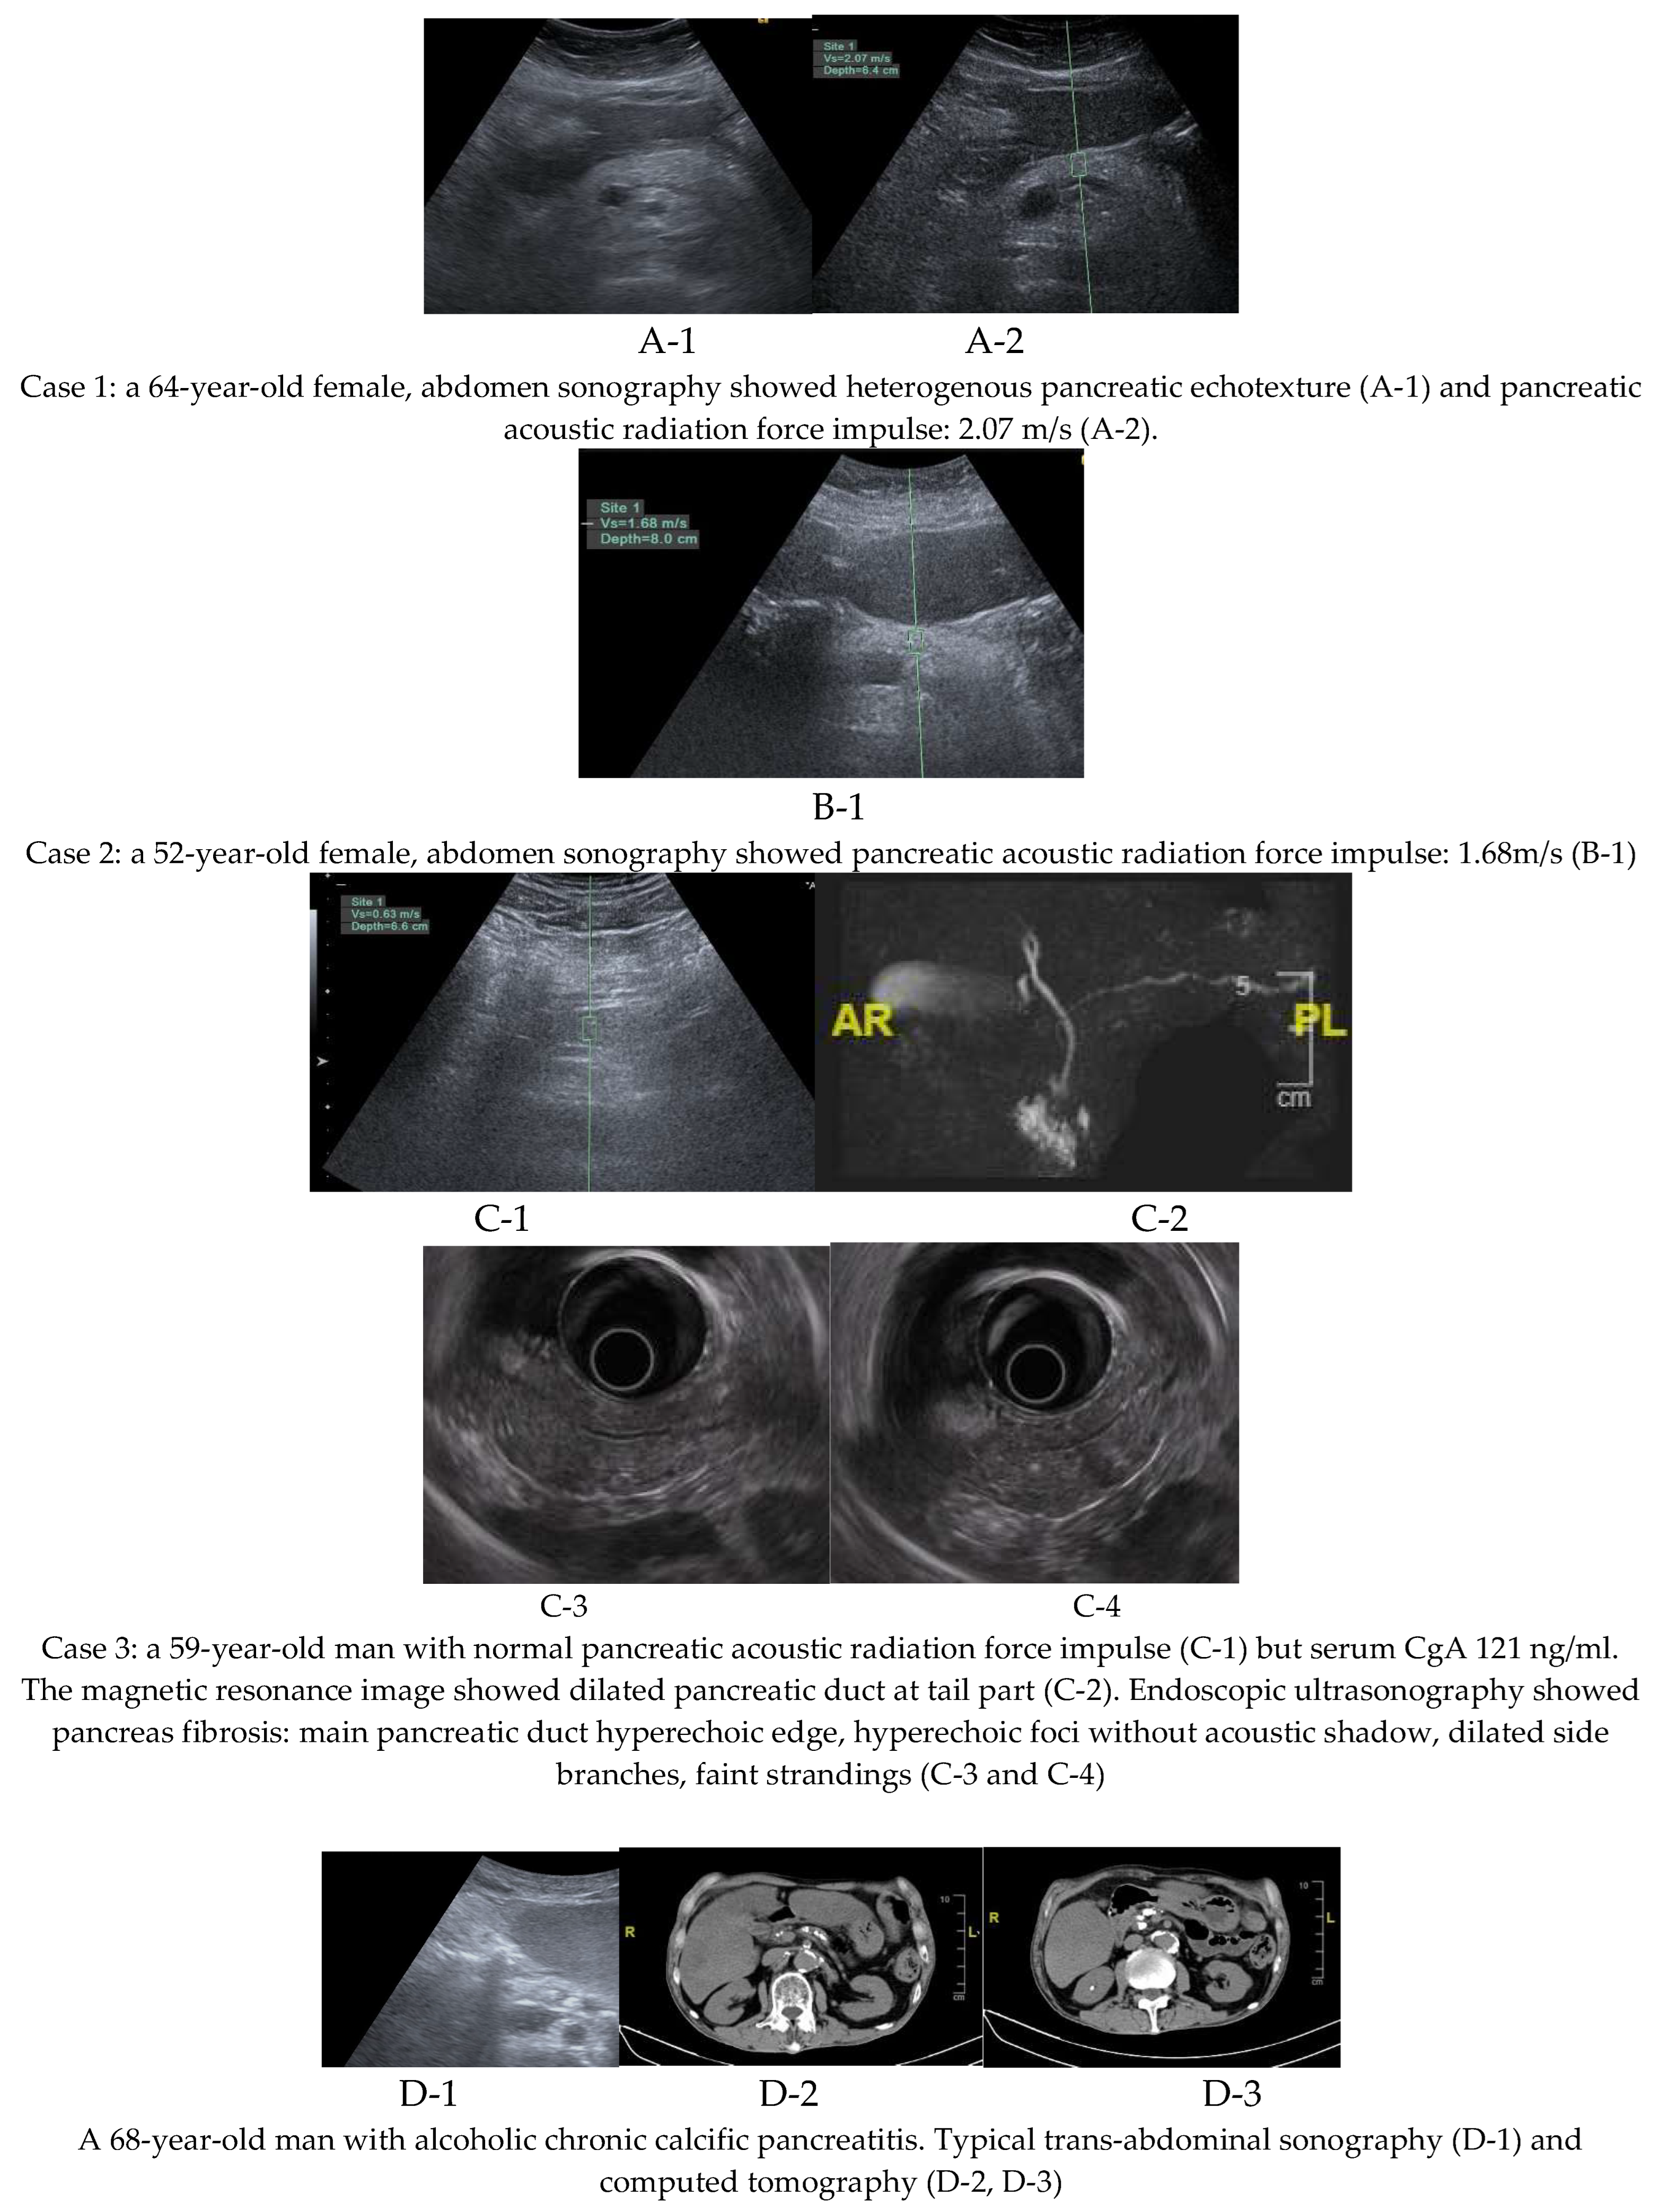

Of the three patients with pancreatic fibrosis, two were diagnosed using pancreatic acoustic radiation force impulse elastography, while one was identified through magnetic resonance imaging performed during surveillance for elevated serum CgA; no pancreatic neuroendocrine tumor was detected in this patient. However, evidence of pancreatic fibrosis was observed, including pancreatic duct dilatation at the tail region. This patient also underwent endoscopic ultrasound examination, which confirmed pancreatic fibrosis. Imaging findings from all three cases of pancreatic fibrosis and one case of chronic calcific pancreatitis are presented in Figure 2.

Figure 2. Images evidence of pancreatic fibrosis (n=3) and chronic calcific pancreatitis (n=1) .